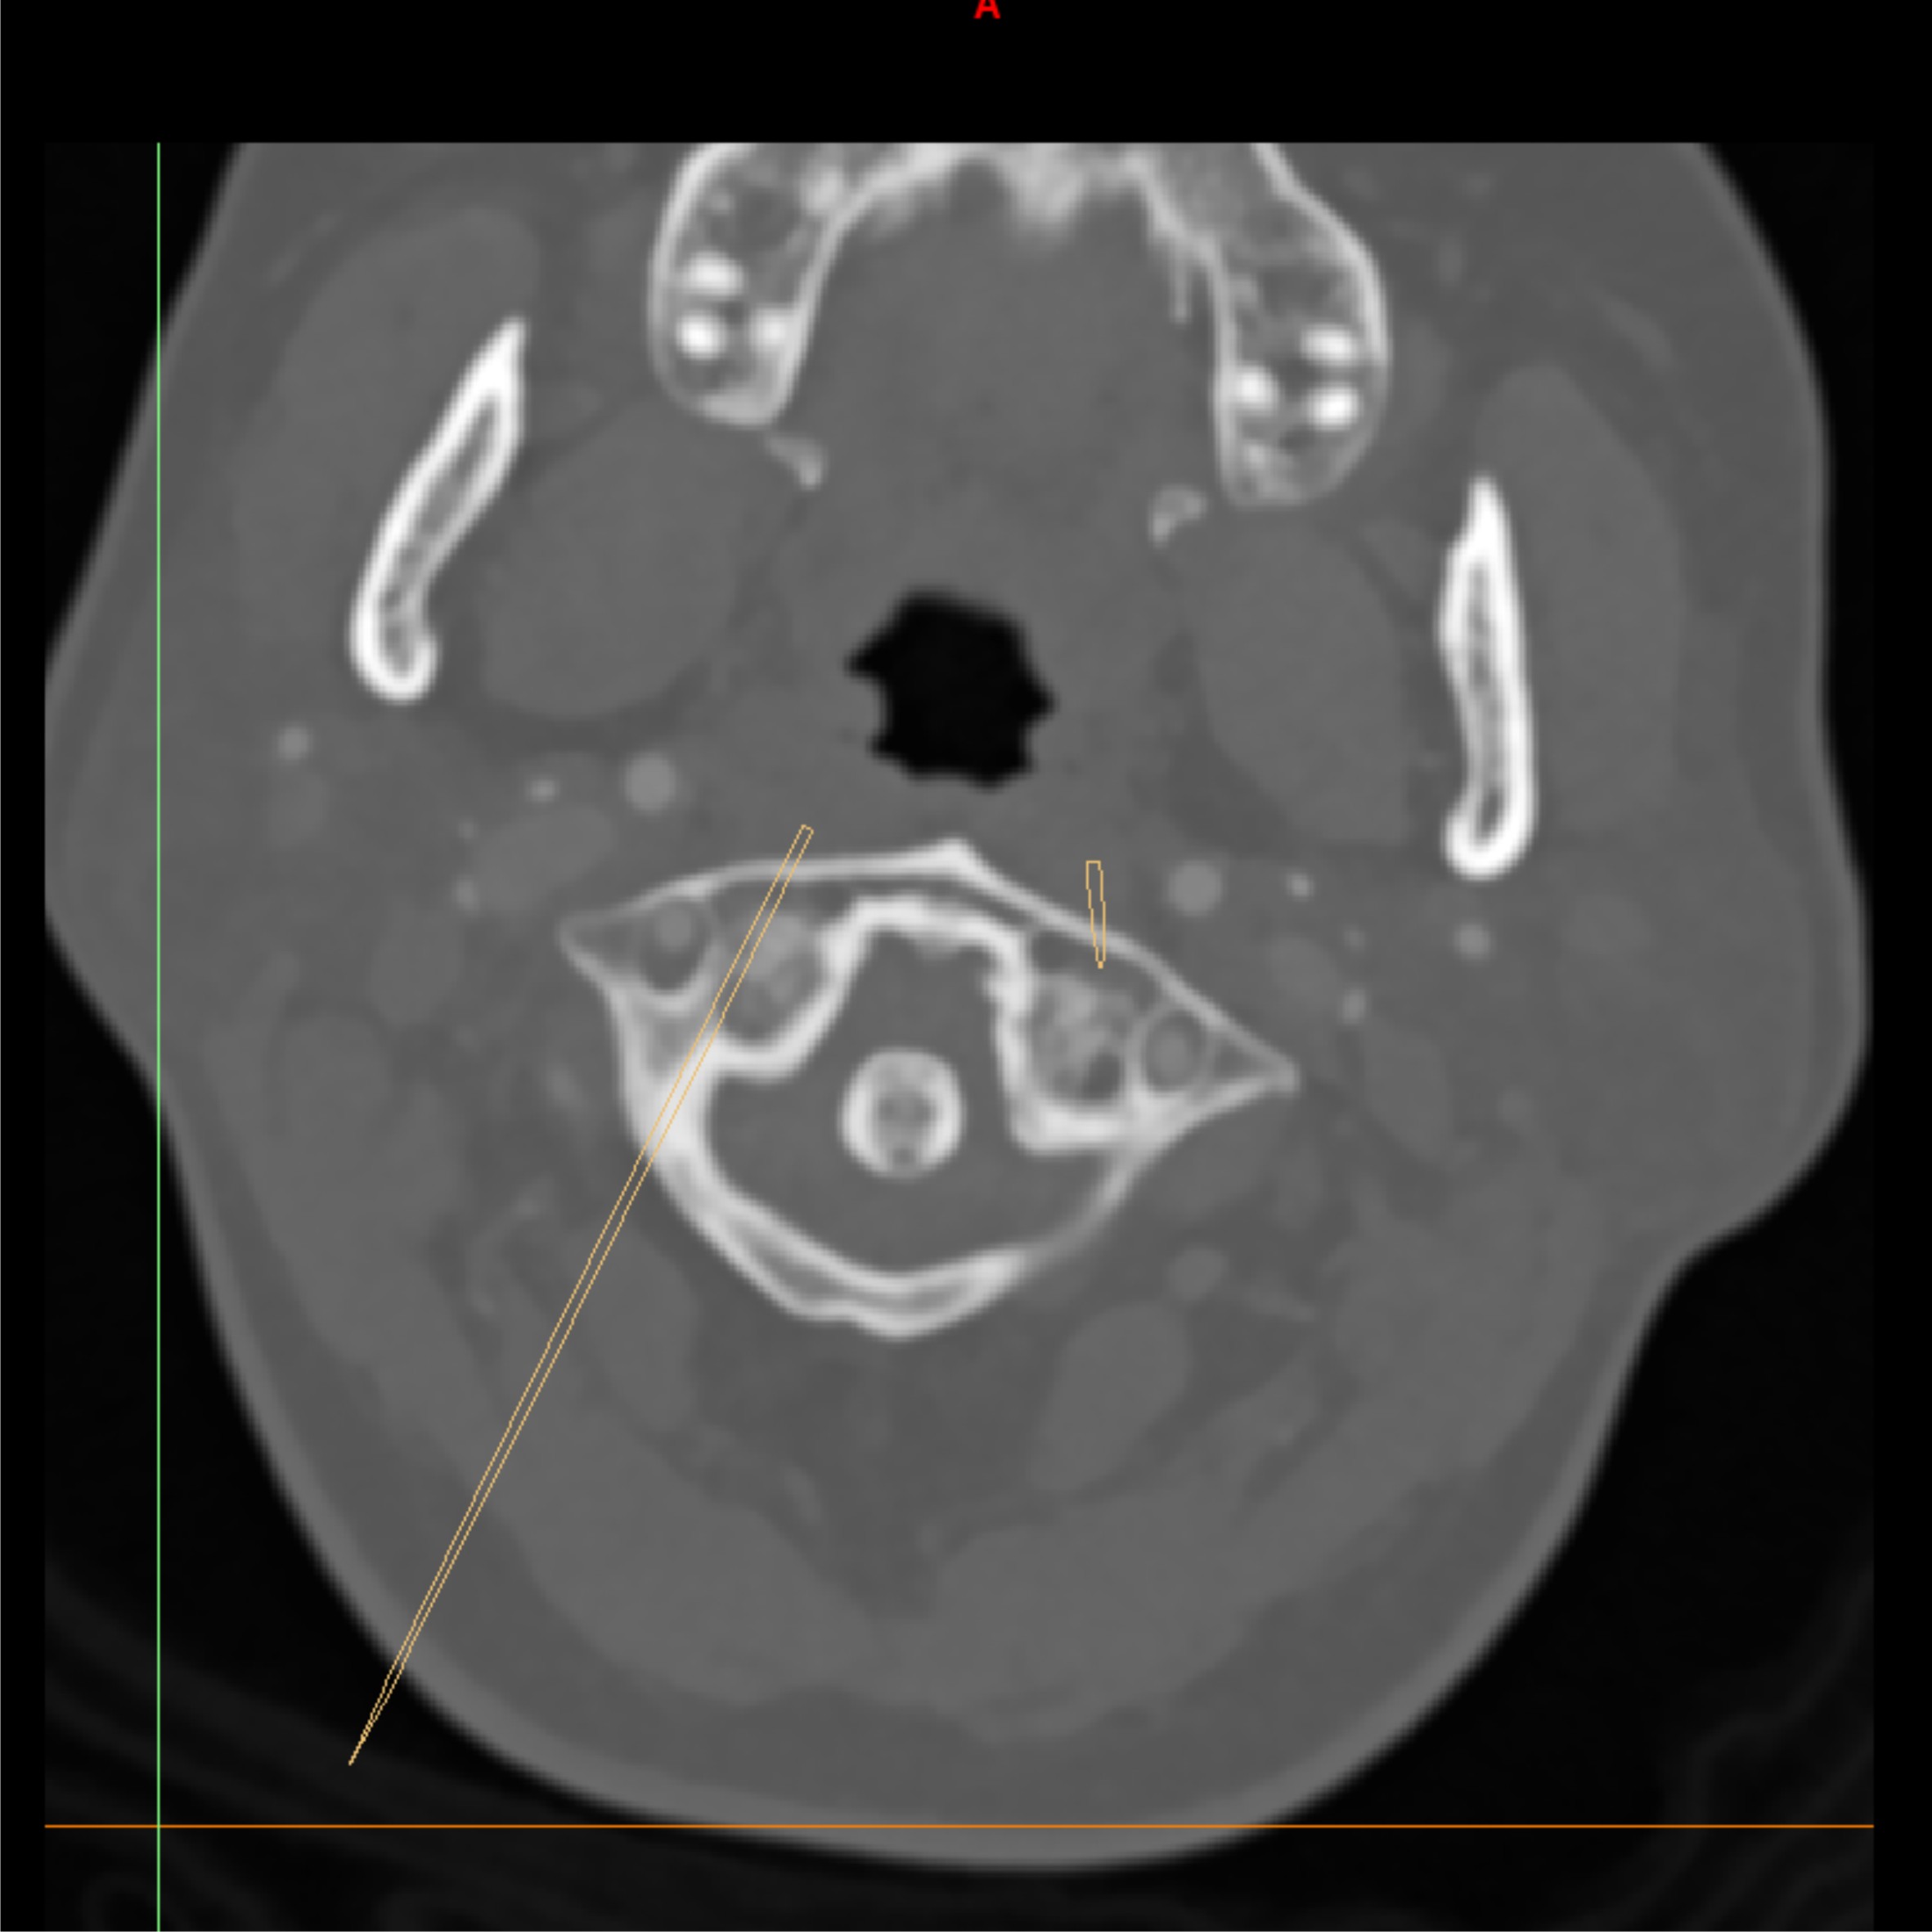

定制化导航板设计

精准定位、导向

术前规划

采集患者CT/MRI数据